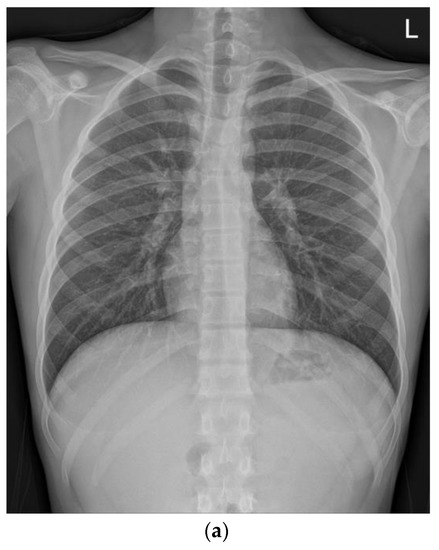

Laboratory tests revealed elevated levels of the following inflammatory markers: white blood cell count, 11,750/mm3 with 68% of polymorphonuclear neutrophils; erythrocyte sedimentation rate (ESR), 40 mm/h; C-reactive protein, 177.7 mg/L (normal, 0–5 mg/L). Although anemia was noted (hemoglobin, 9.9 g/dL), blood chemistry, urinalysis, and stool culture revealed non-specific findings. Additionally, the fecal calprotectin was 3264 µg/g (normal, <50 µg/g). Serologic test for the anti-Saccharomyces cerevisiae antibody revealed equivocal results (IgG 9.3 U/mL and IgA 6.5 U/mL). Chest radiography revealed a normal-shaped heart, and no lung lesions were observed. Abdominal computed tomography (CT) revealed thickening of the terminal ileum and dilated ileal loops. Electrocardiogram (ECG) revealed sinus rhythm with a heart rate of 87 beats/min.

On the second day of hospitalization, he complained of dizziness, chest discomfort, and dyspnea before magnetic resonance (MR) enterography and endoscopy were performed. Vital signs were unstable; blood pressure was 80/60 mmHg, heart rate was 128 beats/min, respiratory rate was 30/min, body temperature was 36.4 °C, and oxygen saturation was 80%. Arterial blood gas analysis revealed a pH of 7.5, pCO2 of 31, and HCO3 of 24.2. Chest radiography and CT revealed pulmonary edema and cardiomegaly (Figure 1).

Figure 1.

Compared with the chest radiography (a) at the time of admission, the chest radiography (b) and low-dose chest computed tomography (c) performed on the second day of hospitalization revealed pulmonary edema and cardiomegaly findings (b).